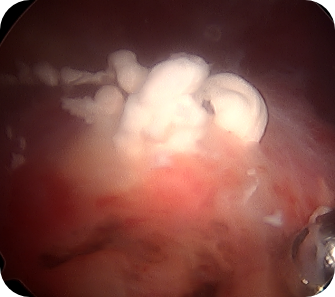

회전근개 질환, 오십견, 어깨 탈구 등 어깨 질환은 어깨의 통증과 고통을 야기합니다. 어깨 관절내시경 수술은 관절 질환이 의심되는 부위를 1cm 미만으로 최소절개한 뒤, 내시경 카메라와 수술 기구를 관절 내부에 삽입해 질환을 진단하고 치료하는 수술입니다. 화면을 통해 병변 부위를 직접 확인할 수 있어 손상 정도에 따라 파열된 힘줄을 봉합하거나 염증을 제거할 수 있습니다. CT나 MRI 등의 진단으로 잘 보이지 않던 곳까지 내시경을 삽입할 수 있어 적용 범위가 점점 넓어지고 있는 추세입니다.

- 관절 내 유리체를 제거할 수 있습니다.